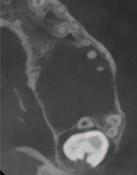

1. What condition is affecting the first permanent molar in Figure 1?

2. What is the estimated global prevalence of the condition according to the European Academy of Paediatric Dentistry (EAPD) Best Clinical Practice Guidelines?

3. List the main aetiological factors that have been linked to this condition.

4. What signs and symptoms of the condition influence clinical management of affected teeth?

Answers on page 45

FIGURE 1: What condition is affecting this first permanent molar?